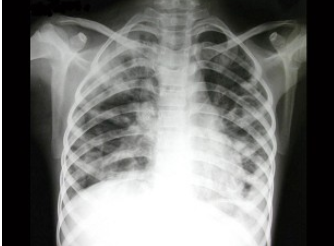

55、单项选择题

男,5岁,高热、畏寒、咳嗽、胸痛1周,如图所示,最可能的诊断为()

E.金葡菌肺炎